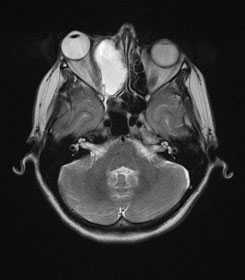

На магнитно-резонансной томографии головного мозга наблюдается увеличение и расширение правого кавернозного синуса и его боковые стенки (указано стрелкой), которое изоинтенсивно на Т1-взвешенной аксиальной томограмме.

На МРТ головного мозга с контрастированием (гадолиний) при тромбозе кавернозного синуса визуализируется гетерогенное усиление (указано стрелкой) на Т1-взвешенной аксиальной томограмме. Наблюдается экзофтальм (выстояние) правого глазного яблока, отек век и утолщение глазодвигательных (экстраокулярных) мышц.

Магнитно-резонансная томография головного мозга во фронтальной плоскости визуализирует тромбоз кавернозного синуса. Видны области множественных нерегулярных дефектов наполнения на участке расширения кавернозного синуса справа, указывающих на наличие тромбов.